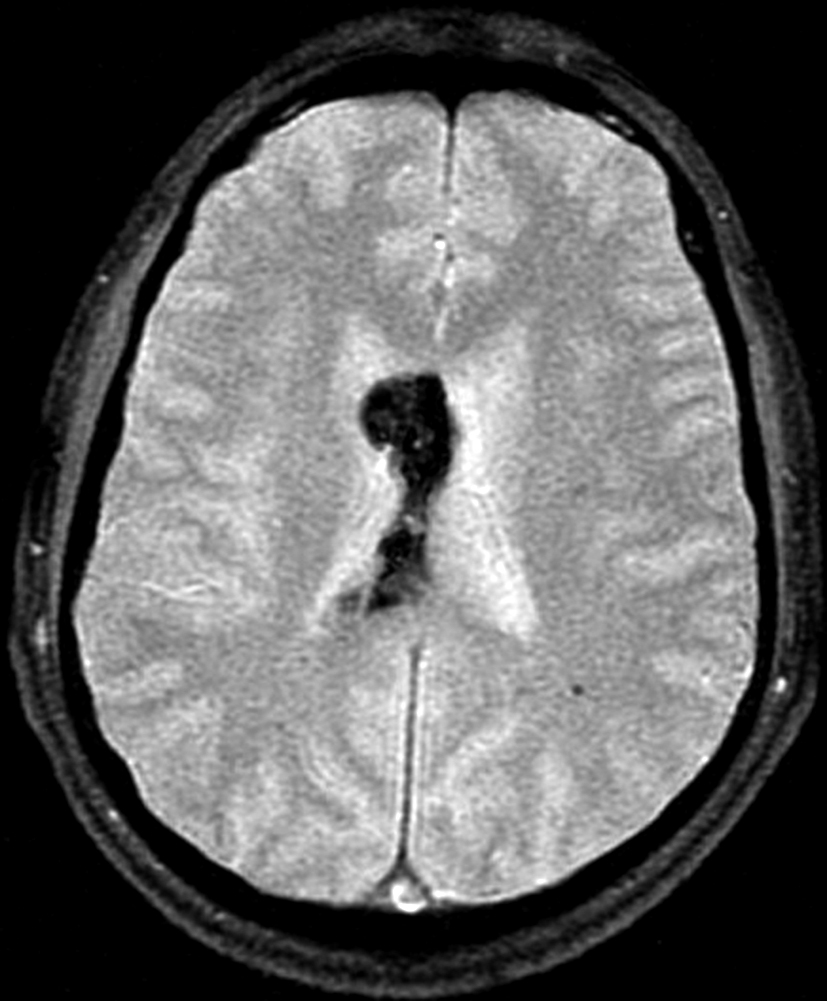

Con los hallazgos tomográficos, no se efectúan planteos diagnósticos y se realiza una resonancia magnética con la finalidad de obtener más datos semiológicos en busca de una aproximación diagnóstica. Se realizó el estudio por medio de secuencias T 1, FSE T 2, FLAIR, SWI y Difusión, en cortes axiales, FSE coronal y sagital T 1. Se realiza la administración de gadolinio DTPA en los tres planos. Se evidencia la lesión bien definida a nivel del ventrículo lateral derecho, que involucra al tronco del cuerpo calloso (Figura 2- C y 3- B). Presenta intensidad de señal heterogénea en secuencias T1 y T2 (Figura 3 y Figura 4). En secuencia ecogradiente se observa una señal marcadamente hipointensa y heterogénea, con un halo hipointenso bien definido (Figura 2- C). No presenta realce significativo tras la administración de Gadolinio (Figura 2- B) y en la secuencia de difusión no presenta restricción.

Figura 4

a y b) Imágenes coronales T2, Ay B. se evidencia la lesión con epicentro en el asta frontal del ventrículo lateral derecho y la extensión al cuero calloso.